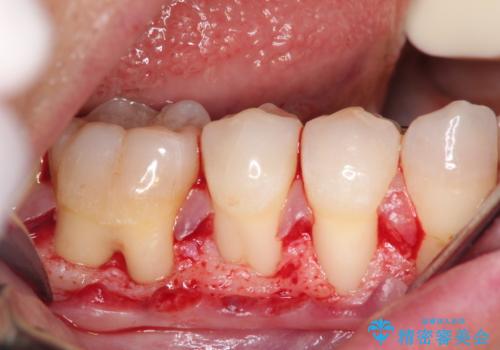

- 昔に受けた矯正治療がきっかけで歯肉が下がってしまった事を主訴として来院された患者様です。

結合組織移植術を行う方法を提案しましたが、傷口が口蓋にもできるのが嫌だとのことで、代替案としてバイオマテリアルを併用した根面被覆術を計画致しました。

治療対象部位は右下4,5,6番の3本です。